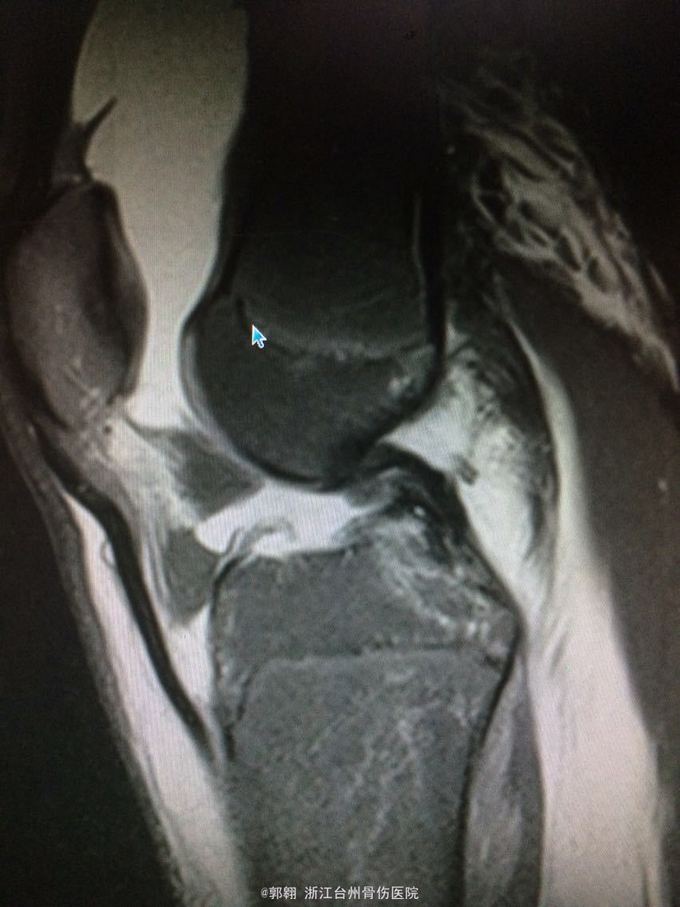

右膝关节跑步摔伤疼痛功能障碍3小时 病史:患者15岁 上体育课时跑步摔倒致右膝关节畸形疼痛 功能障碍,由老师送至医院就诊。

查体:右膝关节及小腿上段肿胀明显,张力较大,压痛位于内侧副韧带股骨处和膝关节外侧,膝关节波动感,浮髌试验阳性、扳膝试验阳性、抽屉试验阳性、Lachman阳性、膝关节屈伸活动因疼痛而障碍,足背动脉波动良好。 MRI:右膝关节股骨内髁骨折 胫骨平台外侧缘骨折

诊断:右膝关节内侧副韧带撕裂 前交叉韧带损伤 股骨内侧髁骨折胫骨平台外侧缘骨折 腓肠肌肌肉拉伤 处理:制动 支具托固定 冰敷 退肿止血药物治疗